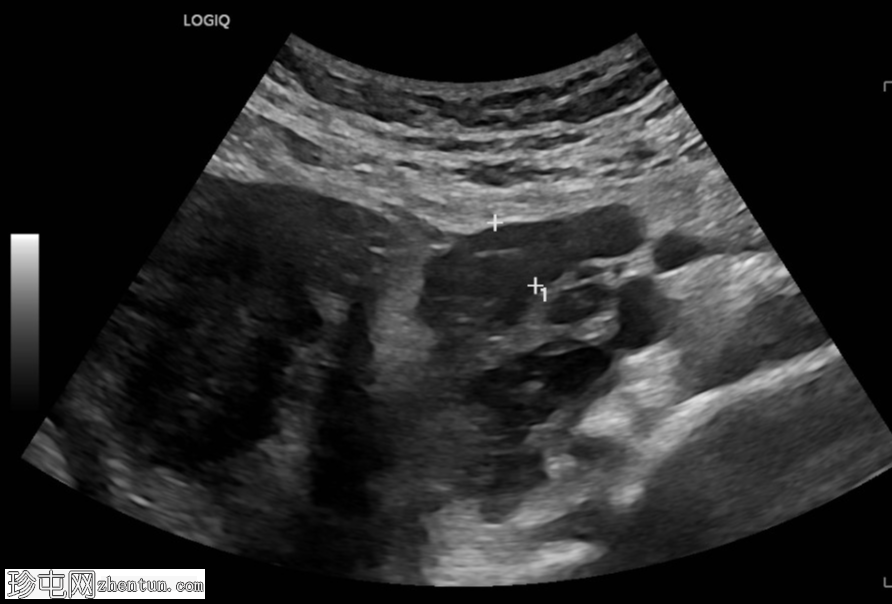

超声检查

横切面

左侧卵巢明显增大,可见一囊肿,大小约3.2 x 2.3 cm,呈火环征,可能为黄体囊肿。左侧卵巢与子宫之间可见一管状结构,直径约1.3 cm,内含浑浊液体,未见血管,最可能为输卵管积血。以上特征提示可能为左侧异位妊娠。

未见宫内妊娠囊。